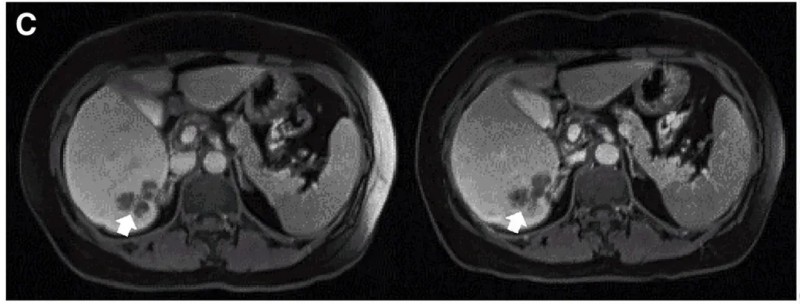

一例P9-2患者:在接受CEA CAR-T回输后,PET/CT显示肿瘤活动减弱、代谢活性显著降低。下图展示了CAR-T输注前(左图)、治疗4周后(右图)的PET/CT对比。

▲图源“Molecular Therapy”,版权归原作者所有,如无意中侵犯了知识产权,请联系我们删除

另一例P10患者:在接受DL4剂量CEA CAR-T治疗后,MRI证实肝内一处病灶缩小。下图展示了CAR-T治疗前(左图)、治疗4周后(右图)的MRI对比。